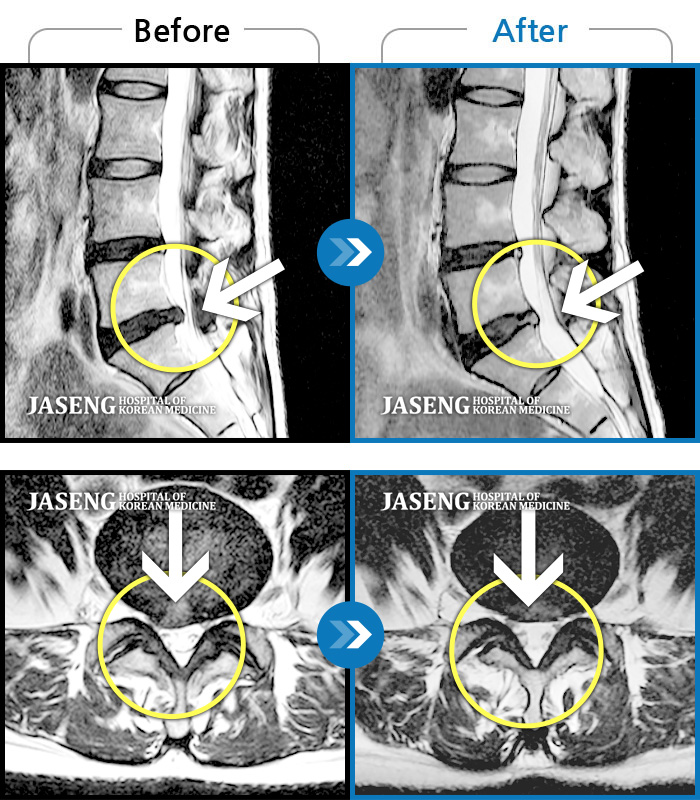

MRI 치료사례

다리가 하루 종일 저려 제대로 걷지 못했다.